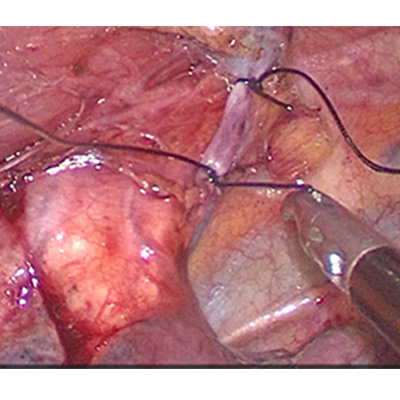

LAPAROSCOPIC SURGERY FOR RECTAL CANCER

ADVANCE LAPAROSCOPIC SURGERY

SURGERY FOR CANCER OESOPHAGUS